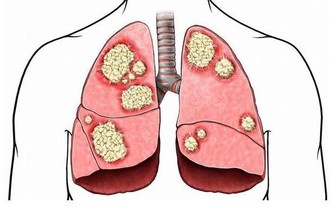

現代人飲食五花八門,容易營養過剩,大家普遍會認為胖不好!但高齡醫學專家表示,「體重稍微肥胖」者(BMI值23-25間)其實死亡率比較低,體重過輕的人因為營養失調,一旦染病就容易有併發症。稍微胖一點,才有本錢對抗疾病,不須太忌口,只要維持好飲食習慣,避免三高(高血壓、高血糖、高血脂)就可以。